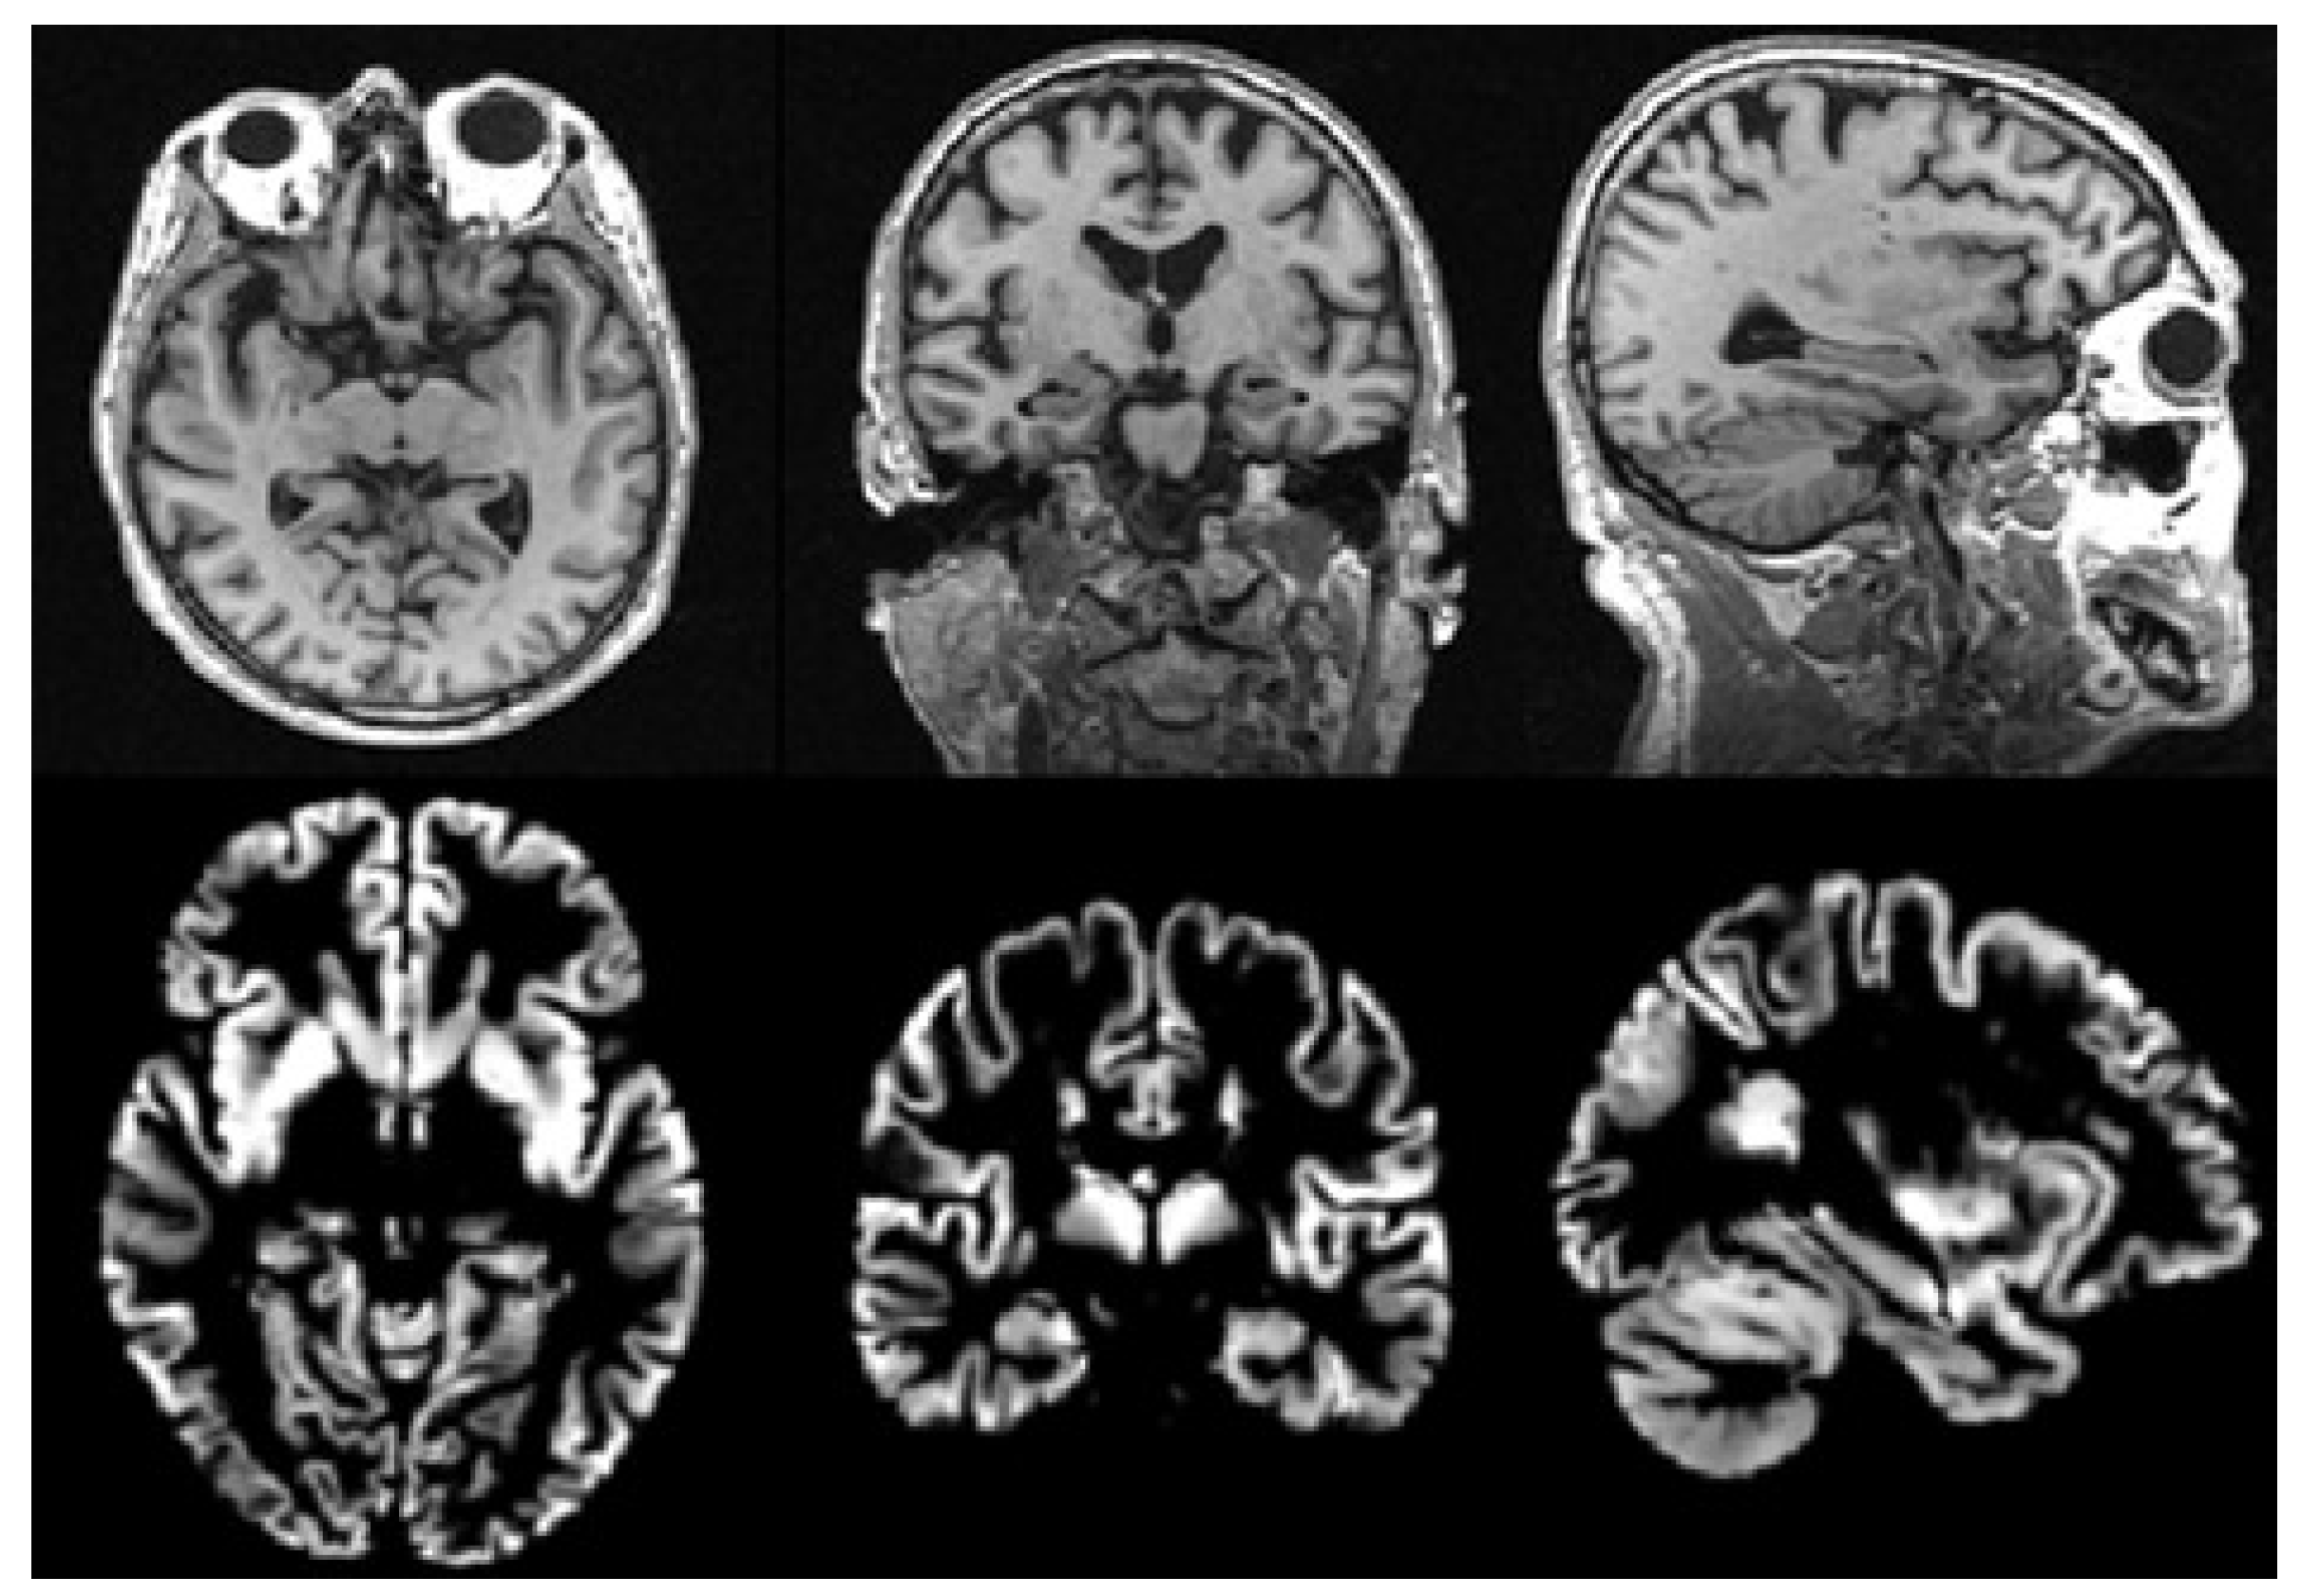

There is usually much noise in the raw data, so we need to preprocess the MRI data first. In this paper, we use the voxel-based morphological preprocessing method. Specifically, we use the CAT12 toolbox which is an extension to SPM12 [44] to provide computational anatomy. First, we register the MRI images to the standard space through DARTEL (Diffeomorphic Anatomical Registration Through Exponentiated Liealgebra) algorithm [45]. Second, we use the maximum a posteriori and partial volume estimation segmentation techniques [46] to segment the image into gray matter, white matter, and cerebrospinal fluid. Then, the Jacobian determinant is used to modulate the gray matter image nonlinearly. Finally, the gray matter image is spatially smoothed with the 8mm Gaussian smoothing kernel. The size of each gray matter image we get in the standard space is 121 × 145 × 121 , then we use scikit-image package to resample it to a size of 96 × 96 × 96 . It is noted that gray matter loss in the medial temporal lobe is characteristic of MCI [47], so we use gray matter images to analyze in this paper. The MRI images before and after preprocessing are shown in Figure 2.

Figure 2. Images before and after preprocessing: The first row shows the original images, and the second row shows the final gray matter images.